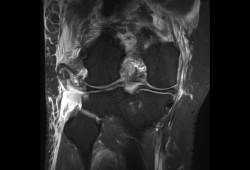

En la osteocondritis se aprecia una lesión subcondral caracterizada por resorción ósea, colapso y la formación de un secuestro.

El estudio por RM es una herramienta valiosa para diagnosticar e identificar las lesiones del cartílago. Conocer el aspecto del cartílago y saber cuánto y cuándo se lesiona, basándose en las clasificaciones actuales, permiten al radiólogo proporcionar la máxima información al clínico(20).

Numerosos estudios demuestran la utilidad de la RM para definir la estabilidad o inestabilidad de la lesión en la osteocondritis, destacando su carácter no invasivo y la capacidad de valorar la progresión y la respuesta al tratamiento(21)(Figuras 53 y 54).

Figura 54. Corte de secuencia T1 y T2 Fat-Sat coronal de resonancia magnética: gran osteocondritis en el cóndilo femoral interno con edema en la medular adyacente.